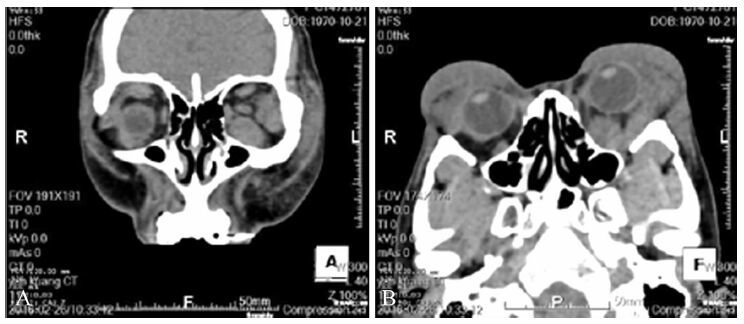

空腹血脂总胆固醇4.90 mmol/L (正常参考范围2.90~5.17 mmol/L)、LDL 2.75 mmol/L (2.70~3.40 mmol/L)、HDL 1.32 mmol/L (0.90~1.68 mmol/L)、甘油三酯1.23 mmol/L (0.56~1.71 mmol/L)。淋巴细胞分类调查,CD3+细胞 (T淋巴细胞标记) 率为85.2%(正常参考范围61%~77%),CD3+、CD4+细胞率在48.2%(正常参考范围27%~57%),CD3+CD8+细胞率在33.6%(正常参考范围14%~34%),CD4+CD8+细胞率为1.43%(正常参考范围1.06%~2.66%)、B淋巴细胞 (B淋巴细胞标记) 率为3%(正常参考范围5%~18%) 和CD3-CD16+CD56+细胞 (NK细胞标记物) 率为9.5%(正常参考范围7%~26%)。眼底检查未见明显异常。胸部X线片显示无异常。CT示双侧眼睑软组织明显肿胀,累及眼眶及眼睑皮下脂肪、眼外肌,包括双侧上直肌,左侧外、下直肌,双侧泪腺和左视神经局部增粗 (图 2)。

|

图 2 1例黄色瘤患者术前眼眶CT扫描 |